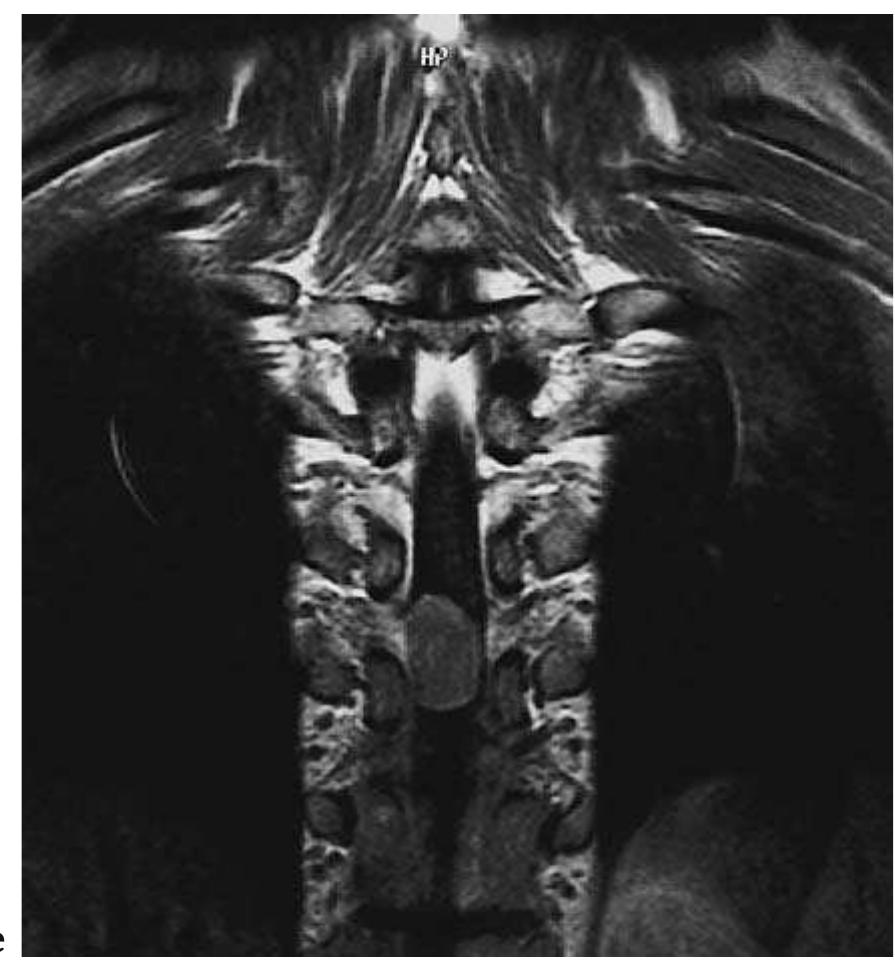

![Fig. 5.45 - Thoracic spinal dural arteriovenous fistula. The MRI study reveals subarachnoid space MRI signal irregularity posterior to the spinal cord, which becomes much more evident on the T2-weighted images due to the presence of serpentine vascular flow voids. [a) sagittal T1-weighted MRI; b) sagittal T2-weighted MRI, c) coronal T2-weighted MRI].](https://figures.academia-assets.com/35610716/figure_445.jpg)